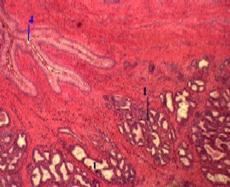

| 3,б-г. Препарат - предстательная железа собаки. Окраска гематоксилин-эозином. | ||

(Малое увеличение) б)Полный размер | (Другое поле зрения) в)Полный размер | (Большое увеличение) г)Полный размер |

| Концевые отделы | 1. По форме концевых отделов (1) ж е лезы простаты являются альвеолярно-трубчатыми. 2. В этих отделах – по крайней мере, три вида клеток: главные клетки – слизистые экзокриноциты кубической или призматической формы, вырабатывающие - все компоненты секрета простаты - и (как полагают некоторые авторы) несколько гормонов (см. выше); базальные, или стволовые, клетки – выглядят как мелкие вставочные клетки; относительно редкие эндокринные клетки, синтезирующие гормоны с паракринным действием. 3. Концевые отделы окружены гладкими миоцитами (2), чьё сокращение облегчает опорожнение концевых отделов при эякуляции. |

| Выводные протоки | 1. Выводные протоки (3), отходящие от концевых отделов, направляются к мочеиспускательному каналу (4). 2. а) У человека они имеют более широкий просвет, чем концевые отделы. б) У собаки же (как видно на снимке) протоки очень узкие. 3. В крупных выводных протоках эпителий - многорядный. |

| Группы желёз | По локализации железы простаты делят на 3 группы: железы в составе слизистой оболочкимочеиспускательного канала; железы в соединительной ткани вокруг мочеиспускательного канала, железы, находящиеся в остальной части простаты (и представляющие собственно предстательные железы). |